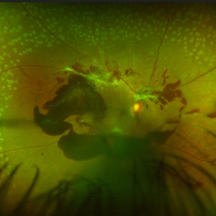

Choroidal Abscess with occlusive retinal vasculitis Choroidal Abscess with occlusive retinal vasculitisJan 28 2023 by Anjana Mirajkar, MS Ophthalmology Widefield color image of LE of a 55 year old male a case of Choroidal abscess with occlusive retinal vasculitis. Photographer: Dr. Anjana Mirajkar -Retina Foundation, Ahmedabad Condition/keywords: choroidal abscess